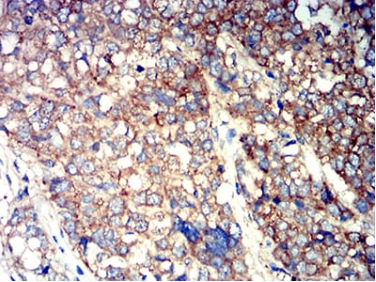

IHC    1/200 - 1/1000